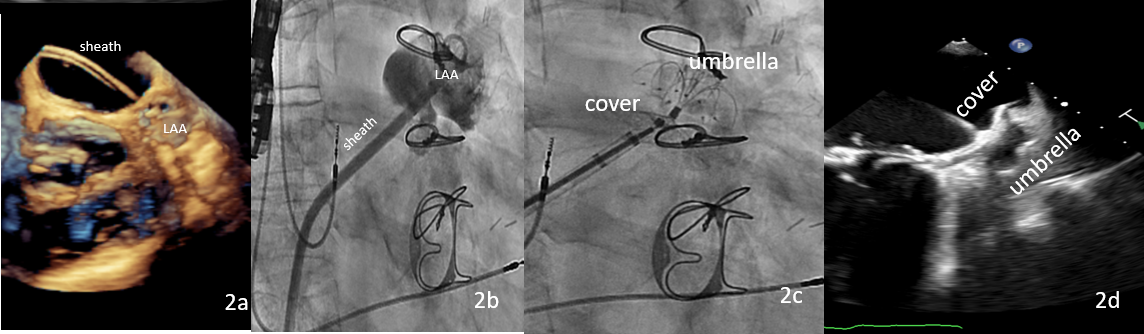

A 79-year-old male (CHA2DS2-VASc = 4, HAS-BLED = 3) with a medical history of atrial fibrillation, dual-chamber pacemaker insertion, coronary artery bypass grafting, biological mitral prosthesis, and surgical LAA ligation in 2021. He was referred for LAA closure due to recurrent major intestinal bleeding with anticoagulation therapy. A transesophageal echocardiogram (TEE) evaluation revealed that the LAA was partially ligated with a residual flow inside (Figure 1A). Computed tomography was performed, which showed a cactus-type LAA with a very narrow ostium (9 x 11 mm) and a wide landing zone (Video 1). The distance to mitral biological prosthesis was 19 mm (Figure 1B and C). A 3D LAA model was made to verify the optimal strategy for this case (Figure 1D), and an inferior and posterior transeptal puncture site was performed (Figure 2A).

The key step of the implantation was to forward the 10-French delivery sheath with a double distal curve of 45 by 30 degrees over the neck (Figure 2B). A 26-mm anchoring umbrella was expanded in the LAA and a 32-mm cover disc was deployed, sealing the ostium (Figure 2C, Video 2). After confirming the distance to the mitral prosthesis and pulmonary vein by TEE (Figure 2D, Video 3), the device was successfully released.